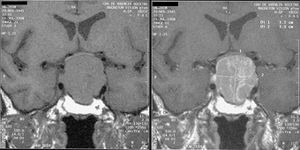

Magnetic resonance image of a pituitary macroadenoma that caused acromegaly with compression of the optic chiasm.